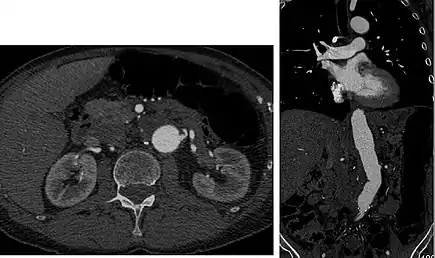

![]() Sagittal thin slice of a computed tomography angiography abdominal aortic aneurysm (AAA) (arrows) | |

Aorta and great arteries

CTA can be used in the chest and abdomen to identify aneurysms in the aorta or other major blood vessels. These areas of weakened blood vessel walls that bulge out can life-threatening if they rupture. CTA is the test of choice when assessing aneurysm before and after endovascular stenting due to the ability to detect calcium within the wall.[3] Another positive of CTA in abdominal aortic aneurysm assessment is that it allows for better estimation of blood vessel dilation and can better detect blood clots compared to standard angiography.[4]

CTA is used also to identify arterial dissection, including aortic dissection in the aorta or its major branches. Arterial dissection is when the layers of the artery wall peel away from each other; this causes pain and can be life-threatening. CTA is a quick and non-invasive method of identifying dissections and can show the extent of the disease and if there is leakage.[4]